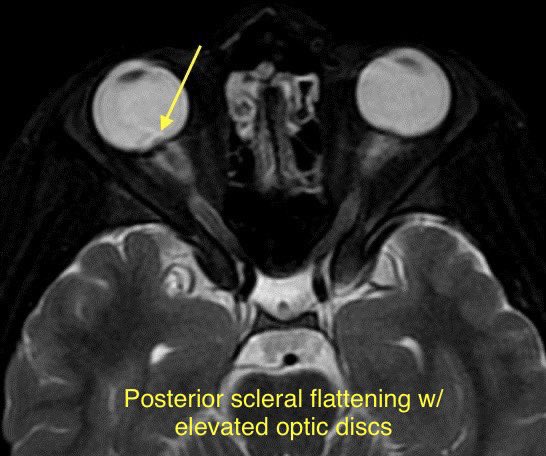

🔷TRANSVERSE SINUS STENOSIS & IDIOPATHIC INTRACRANIAL HYPERTENSION

🔹Tinnitus is present in up to 40-60% of patients with IIH (usually pulsatile and unilateral)

💡Bilateral transverse sinus stenosis is seen in 94% of patients with lIH

💡 Internal cephaloceles are another cause of extrinsic stenosis

💡 Stent placement is safe and effective in patients with transverse sinus stenosis (w/ or w/o lIH)